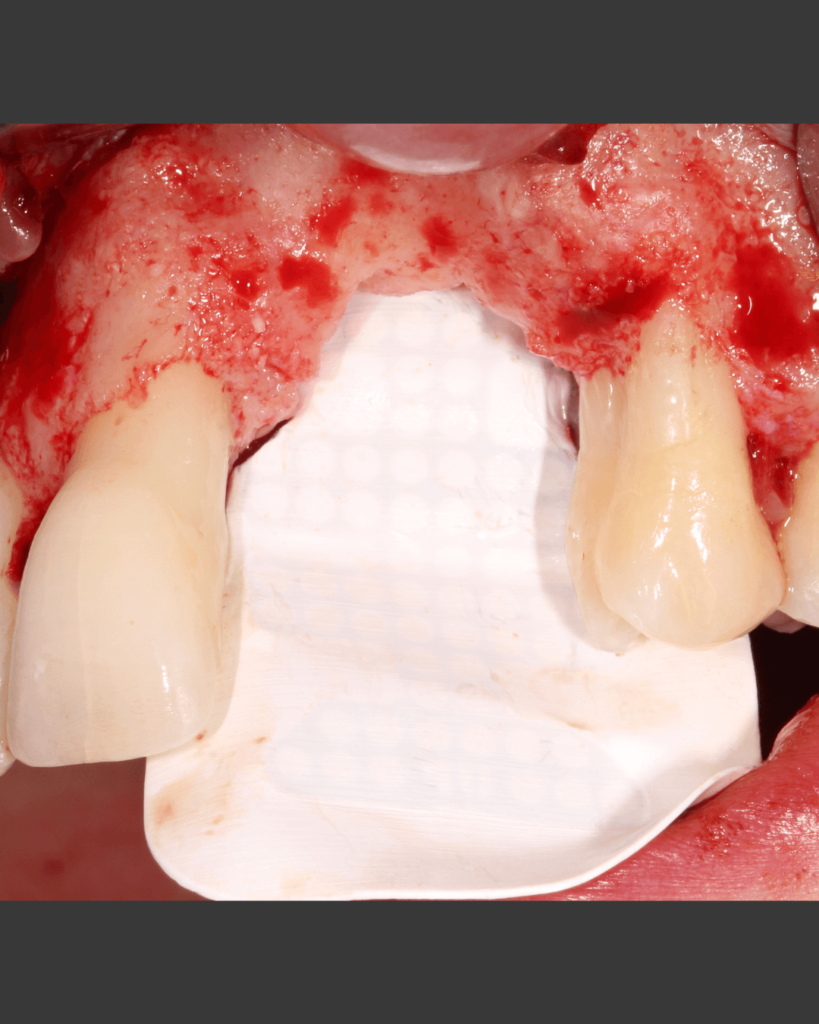

Klinischer Fall

NeoGen® Cape PTFE-Membran, fixiert auf einem gleichzeitig eingesetzten Implantat.

Nach 3 Jahren Entwicklungszeit stellen wir Ihnen die neu entwickelte NeoGen Cape PTFE-Membran vor. Besonders in Fällen von bukkalem Knochendefizit in der ästhetischen Zone ist diese innovative Fixierungsmethode eine hervorragende Lösung für die Behandlung solcher Fälle.

Nachweis einer vertikalen Kieferkammaugmentation bei gleichzeitiger Implantation

Die einzigartige Konstruktion der NeoGen Membranen ermöglicht herausragende klinische Ergebnisse, einschließlich reproduzierbarer und vorhersagbarer Ergebnisse für die anspruchsvolle Indikation der vertikalen Kieferkammaugmentation.